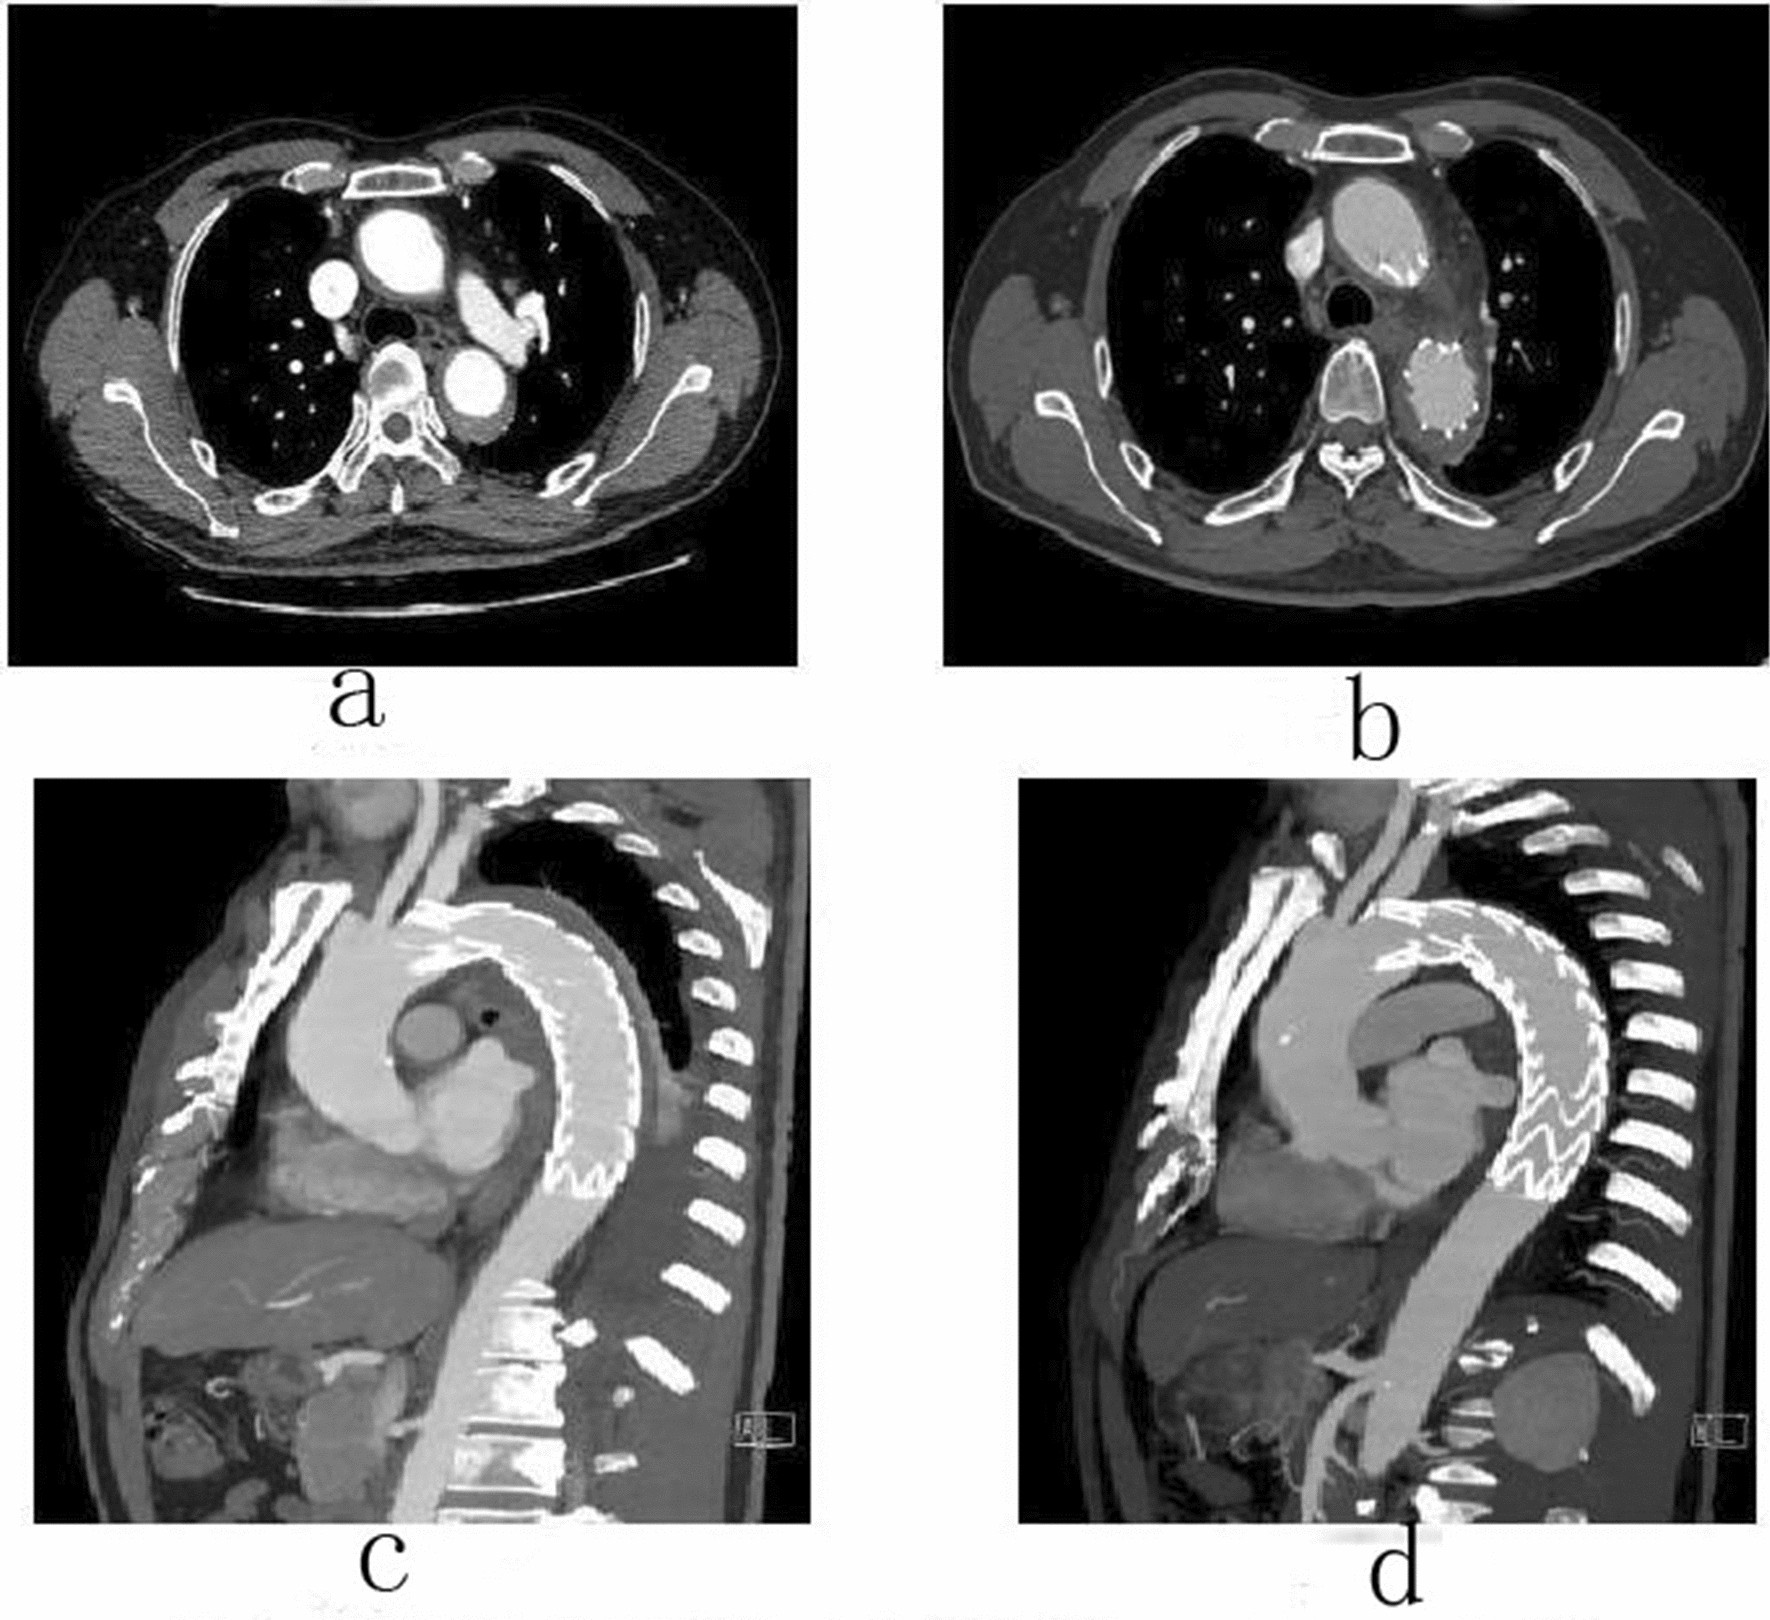

Figure 2

Male, 62 years old, admitted to hospital for “repetition of chest and back pain for 9 h”. Diagnosis: Standford A IMH TEVAR. CTA of the patient in different periods: (a) Admission; (b) 5 days after surgery; (c) 5 days after surgery; (d) 3 months after surgery.